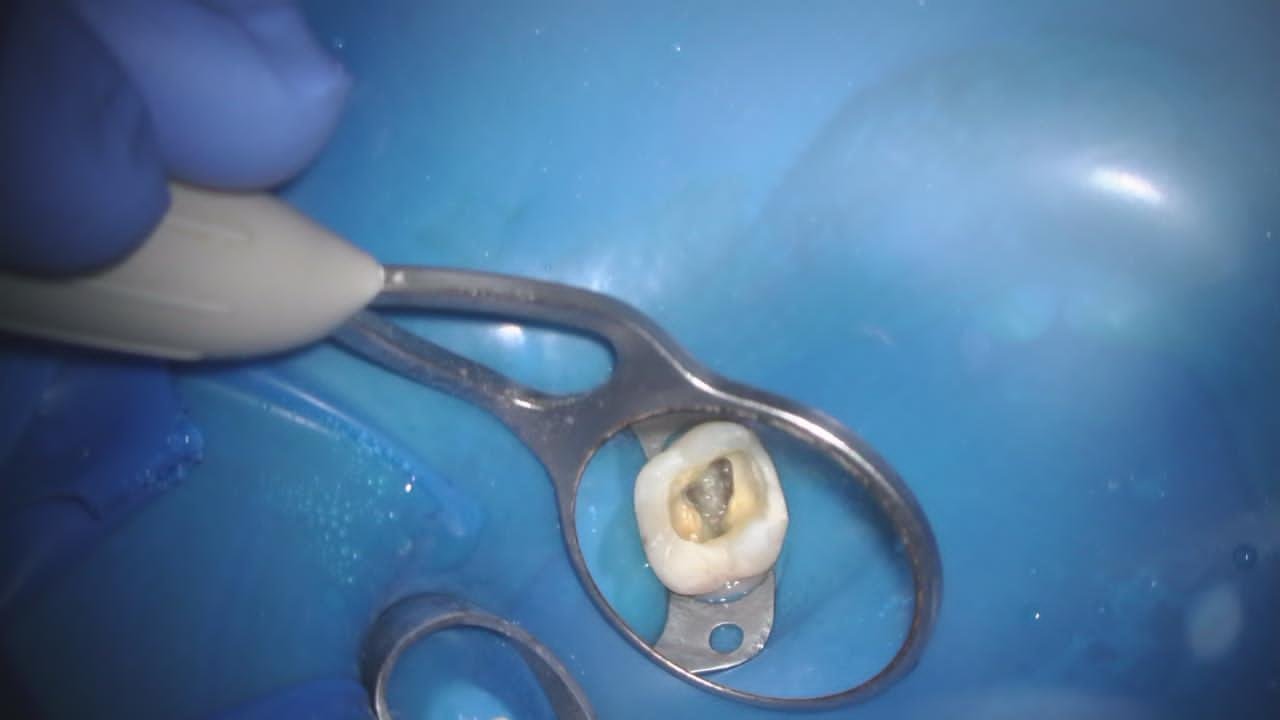

Смотрите, вот зуб на платке, изолирующем его от слюны (к другой стороне зуба всё ещё прикреплён пациент):

А вот так его видно в микроскоп:

Видите? Канал чистый.